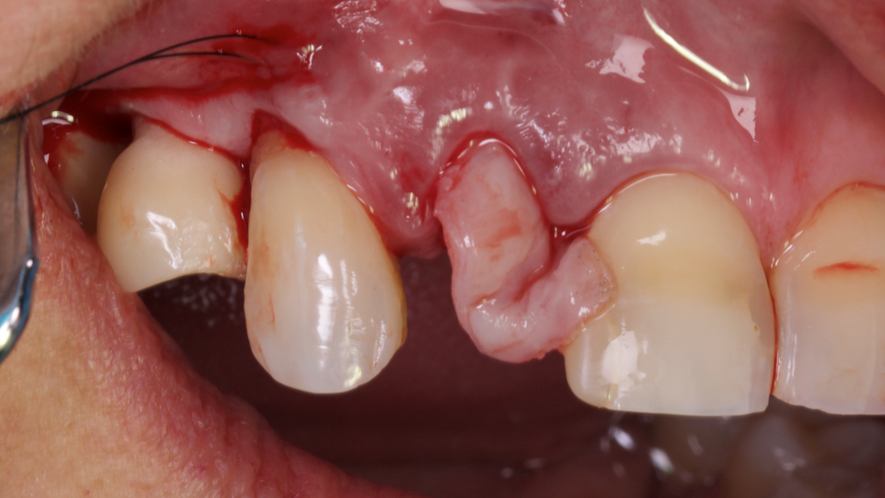

Este trabalho tem como objetivo relatar um caso clínico de exodontia minimamente invasiva de um incisivo lateral superior com fratura radicular, realizando implante imediato em alvéolo pós-extração, enxerto de tecido conjuntivo subepitelial e osso bovino liofilizado para preenchimento de GAP, prontamente à instalação de pilar reto e provisório imediato.